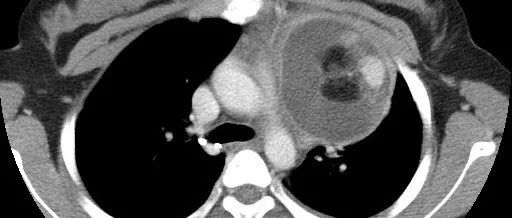

医学影像 yxyx-app 医学影像APP,打造伴随医生快速成长的影像学习社区。与影像园(Xctmr.com)一起提供最全面的影像案例库、基础(解剖、病理、影像诊断)知识、影像技术及考题等,为医生提供最佳的医学影像参考。【所属科室】呼吸科【基本资料】患者,女,20岁【主诉】干咳伴胸痛半月【影像图片】【讨论问题】如何诊断?【医学影像APP用户讨论】评论:左前纵隔见一囊样包块影,内见结节状、条片状脂性密度影,局部囊壁见壁结节影,增强见囊壁及壁结节明显均匀强化;上纵隔脂肪间隙密度增高,但与包块分界尚清,增强后内未见明显强化;肺动脉主干及左侧肺动脉见受压推移,未见充盈缺损影。前纵隔占位,考虑畸胎瘤。...